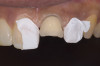

A 20-year-old male patient presented with irregular upper anterior teeth and was unhappy with his smile (Figure 4). He complained of occasional generalized mild sensitivity. Dental treatment history revealed that he had occasional dental work done in the past. Two weeks previously, he had severe pain in tooth No. 10, which was treated endodontically, and he was then referred to the author’s practice for management of anterior wear. Tooth No. 3 had a broken amalgam restoration.

Stone models were fabricated. The upper model was used to do a wax-up on the palatal/labial surfaces of anteriors (Figure 8), which established the lost form of the teeth and had a stop designed for lower incisors so that non-axial forces would be minimized.